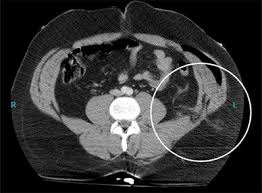

Inguinal Hernia Ct Wikidoc